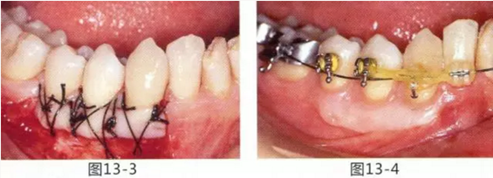

圖14-1 修復體周圍角化牙齦較少,很難進行清潔的狀態(tài),并有緣下齲壞的發(fā)生。

圖14-2,3 徹底去除齲壞后,試圖通過游離齦移植獲取生物學寬度和附著齦。

圖14-4~6修復體周圍角化牙齦較少,很難進行清潔的狀態(tài),并有緣下齲壞的發(fā)生。

圖14-7 配戴最終修復體完成5年后的狀態(tài)。保持良好。